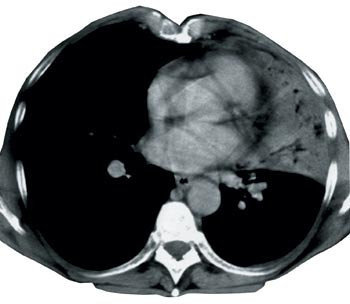

40 undersøkelser (95 %) var utført med intravenøs kontrastinfusjon, mens to var utført uten. Alvorlig kontrastmiddelallergi ca. 20 år tidligere, var oppgitt som årsak hos en av disse. Tre undersøkelser var utført med serier både før og etter kontrastinfusjon. Kontrastfylling i mediastinale kar ble vurdert å være suboptimal hos sju (18 %), men tilfredsstillende hos de resterende 33 (82 %) (fig 1).

Kun 27 (63 %) av undersøkelsene hadde godkjent kvalitet. Dårlig kontrastfylling i karene i mediastinum eller mye bevegelsesartefakter på grunn av langsomt opptak var vanlige årsaker til ikke-godkjent kvalitet (fig 2). Verken de fire undersøkelsene der bare tumor var dekket av serien, eller de to utført helt uten intravenøst kontrastmiddel, ble godkjent. Kvaliteten på undersøkelsen ble likevel vurdert tilstrekkelig god for den aktuelle problemstillingen i tre av sju tilfeller der det på tross av infusjon ikke var optimal fylling av kontrast i mediastinale kar. Andel godkjente undersøkelser var større der spiral-CT var benyttet (22 av 25 undersøkelser, 88 %), sammenliknet med konvensjonell, aksial skanning (fem av 17 undersøkelser, 29 %). Av godkjente undersøkelser var en fra privat røntgeninstitutt, 11 fra lokal- og 15 fra sentral- eller regionsykehus. Av ikke-godkjente undersøkelser (n = 15) var to fra private røntgeninstitutt, 10 fra lokal- og tre fra sentral- eller regionsykehus.